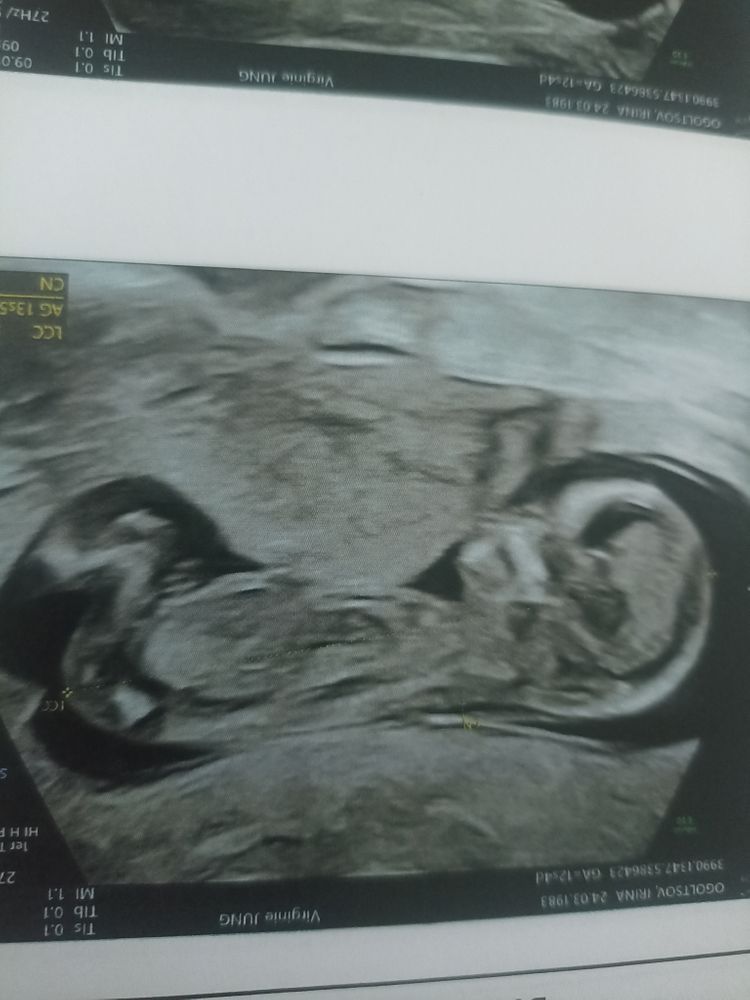

Пол ребенка не увидели, сначала спинкой, потом ножки скрещены были, но врач сказала, что догадывается кто. Следующий раз посмотрим снова.

Ну кто у нас хорошо разбирается в снимках, предположите пожалуйста, хотя я ни бугорка не нашла, ни мошонки, ни хвостика.